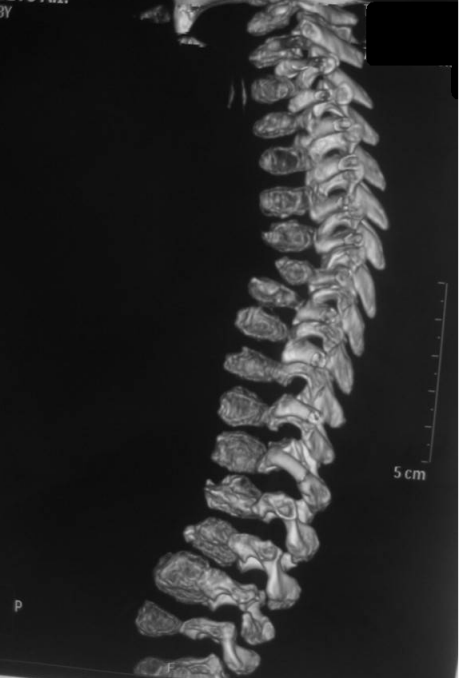

A skeletal survey at the age of 7 years, reformatted coronal spine CT scan showed thoracic scoliosis with significant vertebral disorganization associated with false image of butter-fly like vertebrae of the T8 and L1 and wedging of L2 because of irregular and defective ossification of the vertebral bodies which resembles segmentation defects overwhelmed by extensive enchondromatous lesions along the entire spine and the lacy-like appearance of the iliac crests (Figure 2 [Fig. 2]). Reformatted coronal spinal CT scan showed significant platyspondyly and anisospondyly (irregularly shaped vertebral bodies) in which a unique vertebral disorganization malformation complex is notable. Specific feature – chondromatose nodes in vertebral bodies (bony “defects” in anterior aspects, mostly – at thoracic level) (Figure 3 [Fig. 3]). Antero-posterior (AP) standing radiograph showed hypoplastic iliac bones associated with severe epiphyseal dysplasia and enchondroma-like lesions metaphyseal changes with significant metaphyseal expansion and radiolucency of the inferior femora. Note the windswept lower limb deformity (abnormal valgus deformity in one knee in association with varus in the other) (Figure 4 [Fig. 4]). Contrast arthgrography of the hips demonstrates spherical shape of the femoral heads with severe delayed ossification. Congruency of the hip joints is normal, cartilaginous acetabular coverage is sufficient. Short femoral necks (more severe on the left side with secondary decreased neck-shaft angle) are notable (Figure 5 [Fig. 5]). Contrast arthrography of the hips was done to assess cartilaginous components of the hip joints as a part of the previous pre-operative protocol which was standard in our clinic for children with severe hip instability. Now we believe that MRI would be less invasive and a more useful investigation in such a case. Nevertheless our data demonstrates spherical shape of the femoral heads with severe delayed ossification. Congruency of the hip joints is normal, cartilaginous acetabular coverage is sufficient.